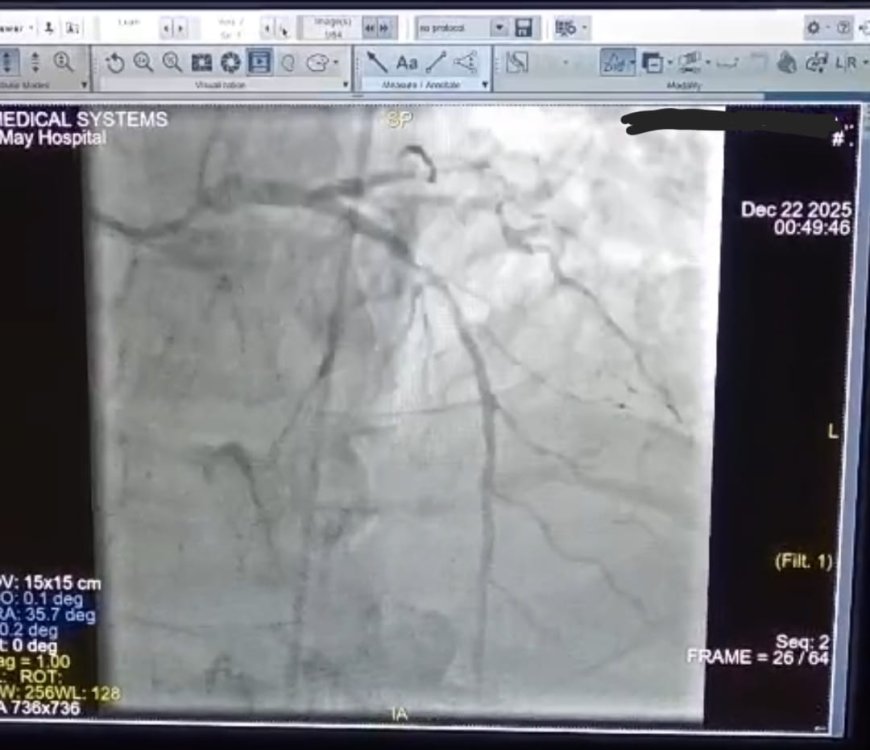

بكل فخر واعتزاز، تُعلن مستشفى ١٥ مايو النموذجي عن إنجاز طبي استثنائي ، نجح قسم القلب، برئاسة الأستاذ الدكتور أحمد جعفر، في إنقاذ حياة مريض كان في حالة حرجة بعد إصابته بـ:

جلطة قلبية حادة مكتملة بالشرايين التاجية نتج عنها توقف بعضلة القلب.

تم على الفور بقسم الطواريء بدأ الانعاش القلبي الرئوي وتركيب انبوبة حنجرية حتى تم استعادة النبض وسرعان ما تم تفعيل بروتوكول القسطرة القلبية الطارئة وتم نقل المريض إلى وحدة القسطرة القلبية وتم إجراء قسطرة لفتح الشريان الرئيسي وتركيب دعامتين دوائيتين.